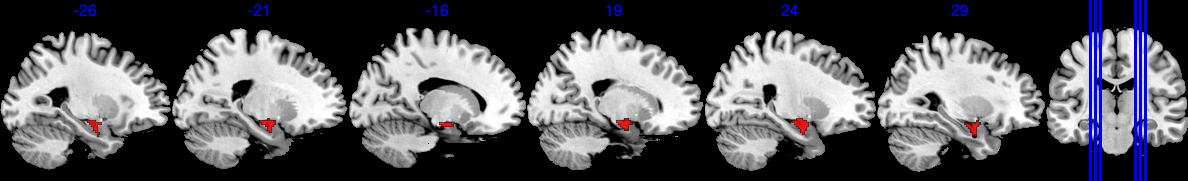

4.2.2 Focused Results: Amygdala Region

The amygdala region is part of the limbic system. They are responsible for detecting danger and negative emotions, and play an important role in behavior, emotional control, and learning (Bzdok et al., 2013). The emotion task fMRI data in UK Biobank is based on emotion tasks where participants are asked to identify faces with negative emotions. Hence we expect the amygdala region to play an important role. The amygdala region is a small area in the brain, as shown in Figure 4(a), containing 380 voxels out of a total of 121,865 voxels.

Based on the results shown in Figure 4, SBIOSimp identifies a large proportion of voxels in the amygdala region to be active. Numerically, SBIOSimp identifies 324 out of 380 voxels in both the left and right amygdala to be active with . From the highlighted box in Figure 4(b), the active voxels mostly concentrate on the direction where the amygdala region connects to the parahippocampal gyrus, anterior division. The anterior portion of the parahippocampal gyrus is involved in complex emotive processes and has significant interconnectivity with other cortical limbic structures and the amygdala (Kaas, 2016). Figure 4(c) shows the yellow-shaded area within the amygdala in which voxels are associated with at least 50% decline in the brain signal intensity for 10-year increase in age from 50.